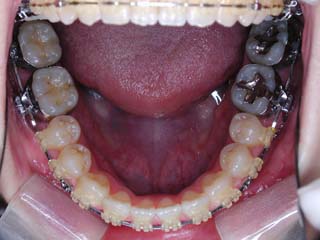

before |

一般的な外科矯正治療の流れは、術前矯正・外科矯正・術後矯正・保定治療と移行します。術前矯正では、手術を行う時点で、上下がぴったり合うような歯列に仕上げる事になりますので、逆に言えば、手術をしていない直前においては、とんでもなく噛めない状態となっている事が多いです。このケースでは下顎のみのセットバック(後退術)をSSROにて行いました。 |